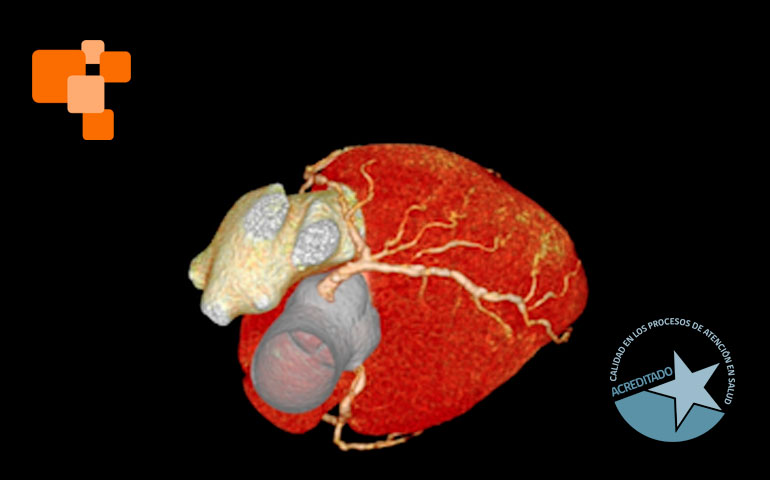

El TAC de calcio coronario es un examen de alta complejidad, realizado usualmente en centros de imagenología avanzada, mide el calcio en las arterias coronarias para evaluar el riesgo de eventos cardíacos futuros. Al proporcionar un score de calcio coronario, permite a los médicos identificar la acumulación de calcio y ajustar tratamientos para prevenir la aterosclerosis, una causa principal de ataques cardíacos. Según expertos, médicos especialistas en cardiologías lo sugieren principalmente para aquellos en riesgo moderado, pacientes que no han tenido síntomas, pero poseen factores de riesgo como hipertensión o colesterol alto.

La tomografía computada para el cálculo del score de calcio coronario permite identificar y cuantificar calcificaciones antes de que se manifiesten síntomas de enfermedad cardíaca, facilitando intervenciones tempranas. Es una técnica de diagnóstico por imagen que, a diferencia de otros métodos más invasivos, ofrece una evaluación rápida y no invasiva de las coronarias.

TAC coronario

La elección de un centro de imagenología avanzada es crucial para asegurar la precisión del TAC de calcio coronario. En Centro de Diagnóstico San Lorenzo, nuestra infraestructura se encuentra equipada con la tecnología más avanzada, un TAC de 128 canales con inteligencia artificial, y todo un personal calificado que garantizan la calidad y fiabilidad de los resultados, aspectos fundamentales para un diagnóstico y tratamiento adecuado que recomendará su médico de cabecera.